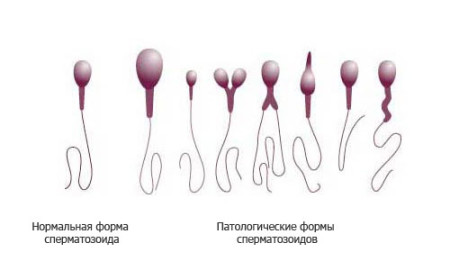

Причиною припинення розвитку ембріона і подальшої його загибелі може бути і не відбувся батько. Наявність такої патології, як тератозооспермия найчастіше є причиною безпліддя партнера, проте в деяких випадках вагітність може виникнути, але в більшості випадків вона закінчується викиднем. Тератозооспермія - це патологічний стан сперматозоїдів, при якому вони мають неправильне будова. Аномалії сперматозоїдів можуть проявлятися у вигляді потовщення або перегину хвостика, відсутність хромосоми, наявності в голівці вакуольна клітин, неправильної форми головки, короткого хвоста.

Про тератозооспермії кажуть в разі наявності в еякуляті пацієнта більше 50% (в більшості випадків близько 80%) аномальних сперматозоїдів. Зачаття в таких випадках або взагалі неможливо, наприклад, через те що сперматозоїди з коротким хвостиком втрачають свою рухливість, або ж яйцеклітина запліднена, але внаслідок аномалії головки сперматозоїда ембріон розвивається неправильно і прогресування вагітності припиняється. Після обстеження і терапії багато пар все ж змушені звертатися до додаткових допоміжних репродуктивних технологій, наприклад, штучної інсемінації.